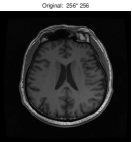

Besides the Shepp-Logan phantom image, we also tested Cameraman, Lena, Boat, Sailboat, as well as two brain images. In this experiment, we simply set and keep all other parameters unchanged. The original and the recovered images by TwIST and IADM are given in Figures 3 and 4, and detailed results including relative errors (RE), CPU time (Time), final objective function values (Obj), and the number of iterations (Iter) are presented in Table 2. It can be seen from Table 2 that IADM attained comparable or better image quality in less CPU seconds. For each test, IADM consumed more iterations while the CPU time is less because the per-iteration cost of IADM is much less than that of TwIST. Specifically, the per-iteration cost of IADM contains two matrix-vector multiplications and two FFTs, while TwIST needs to solve a TV denoising problem at each iteration. In addition, IADM always attained smaller function values. In summary, the comparison results indicate that IAMD performs favorably and can be competitive with the state-of-the-art algorithm TwIST.

| TwIST | IADM | ||||||||

|---|---|---|---|---|---|---|---|---|---|

| Images | Size | Iter | RE | Time | Obj | Iter | Re | Time | Obj |

| brain 1 | 52 | 14.01% | 34.25s | 4.7831e+002 | 208 | 13.64% | 20.41s | 4.5478e+002 | |

| brain 2 | 48 | 9.59% | 90.22s | 1.6397e+003 | 176 | 9.45% | 61.67s | 1.5665e+003 | |

| cameraman | 56 | 5.71% | 122.22s | 2.9068e+003 | 257 | 5.59% | 118.67s | 2.7822e+003 | |

| lena | 53 | 4.93% | 121.06s | 2.3656e+003 | 205 | 5.01% | 92.11s | 2.2627e+003 | |

| man | 59 | 8.54% | 423.38s | 1.0617e+004 | 262 | 8.57% | 400.81s | 1.0122e+004 | |

| sailboat | 57 | 4.91% | 361.58s | 7.9220e+003 | 245 | 4.98% | 260.73s | 7.5960e+003 | |

| sheppon | 42 | 2.62% | 335.36s | 4.4496e+003 | 135 | 2.09% | 217.08s | 4.2317e+003 | |

| boat | 53 | 4.37% | 477.17s | 8.7306e+003 | 200 | 4.34% | 384.61s | 8.3312e+003 | |

| barbara | 56 | 9.83% | 493.20s | 1.3469e+004 | 292 | 9.80% | 550.39s | 1.2814e+004 | |